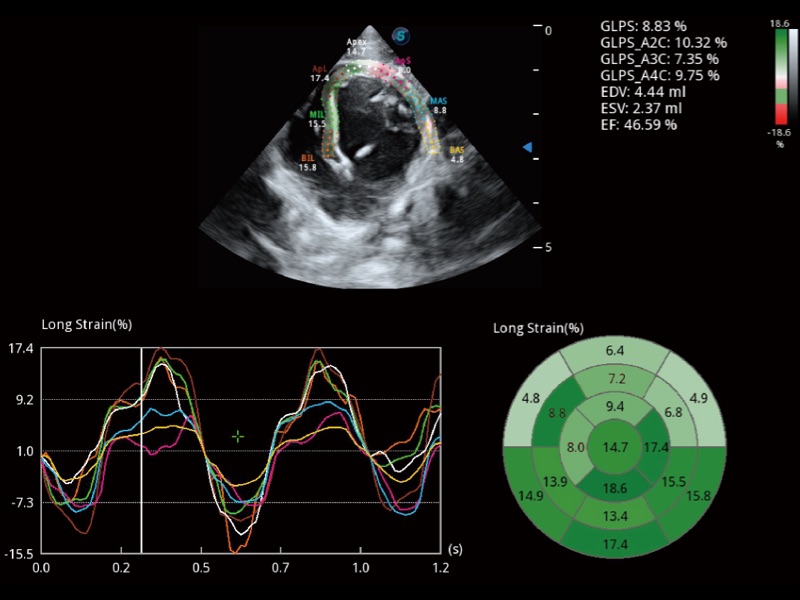

能夠基于左心室壁追蹤和辛普森法,自動(dòng)計(jì)算射血分?jǐn)?shù),支持多個(gè)可移動(dòng)點(diǎn)描跡,與手動(dòng)測(cè)量相比,極大節(jié)省了動(dòng)物醫(yī)生的時(shí)間和精力。

具備多種協(xié)議可選,同時(shí)支持17階段劃分法和專(zhuān)業(yè)的SE報(bào)告。

實(shí)時(shí)用顏色表示心肌組織運(yùn)動(dòng),觀察和定量組織的運(yùn)動(dòng)情況,對(duì)快速檢測(cè)與評(píng)估心肌的灌注和活性、電傳導(dǎo)及心肌收縮和舒張功能等均能提供重要的診斷信息。